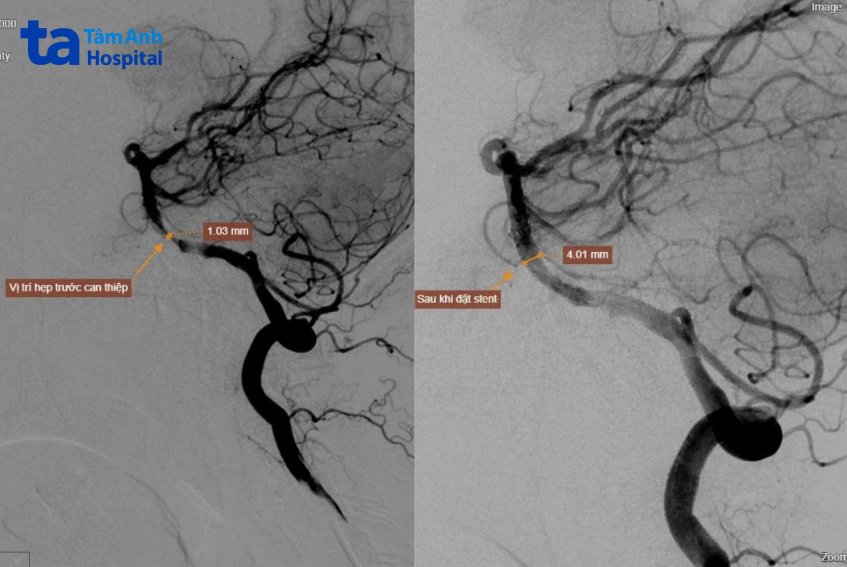

Ekip định vị tổn thương trên phim chụp mạch số hóa xóa nền và chụp mạch 3D để xác định chính xác vị trí và kích thước đoạn hẹp. Sau đó bác sĩ tiến hành nong nhiều lần, từng chút một để tránh tổn thương tối đa lên mạch máu. Sau 30 phút, bác sĩ nong mạch an toàn, đặt stent thành công vào phần mạch bị hẹp khít. Kiểm tra lại bằng máy chụp mạch máu cho thấy máu lưu thông tốt, không có tai biến hay tắc các nhánh lành.